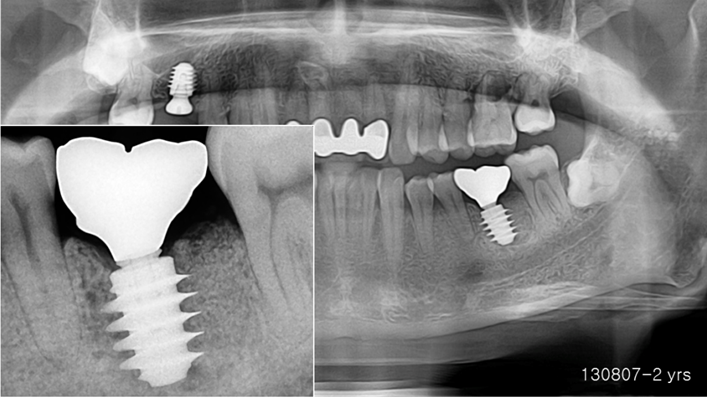

Clinical case: Bone growth in deepest thread of 8.0mm AnyRidge fixture

- Courtesy of Dr. Kwang Bum Park -

Clinical case: Bone filling into the bottom of deepest thread at 8.0mm AnyRidge fixture

Keywords

AnyRidge, Knifethread ,extraction socket, ,initial stability ,Allograft, ,osseointegratio ,Dr. Kwang Bum Park, , Mandibular, Single replacement, AnyRidge, Mega-oss,

Products used

Implant system-AnyRidge, Regeneration-Mega-Oss